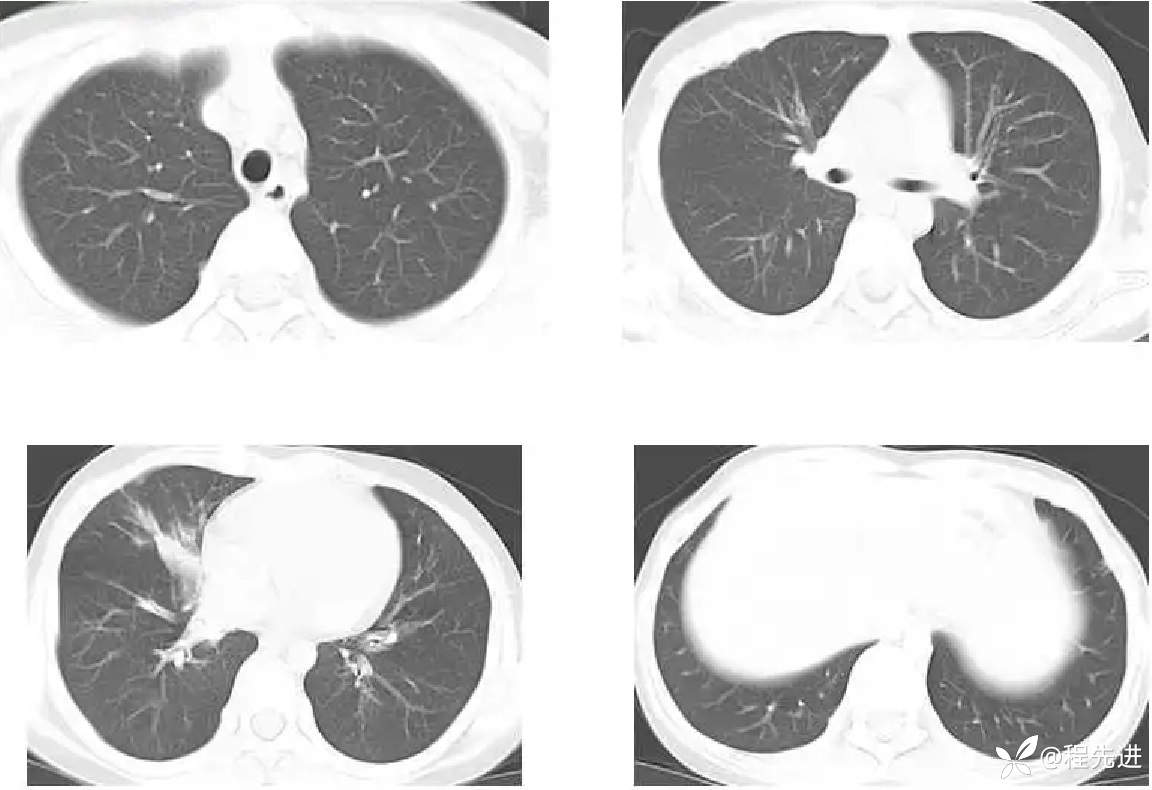

患者性别:男

患者年龄:11岁

简要病史:受凉后发热3天

既往史:生长发育迟缓

胸部CT: